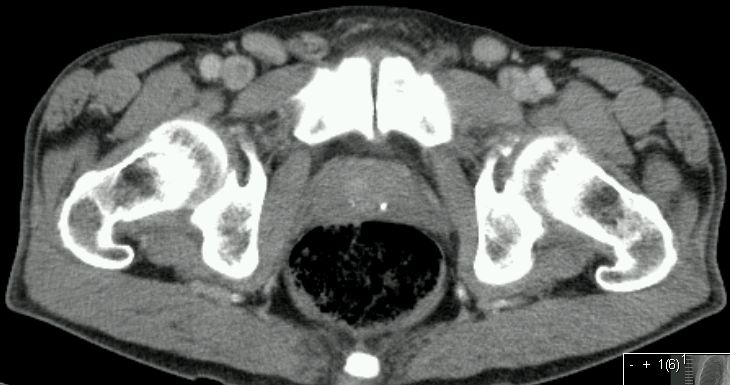

inguinales Lymphknotenrezidiv

95-jähriger Mann, beim vor 9 Monaten ein Plattenepithelkarzinom der Vorhaut entfernt wurde. Jetzt in beiden Leisten faustgroße, zentral zystisch zerfallende Lymphknotenpakete.